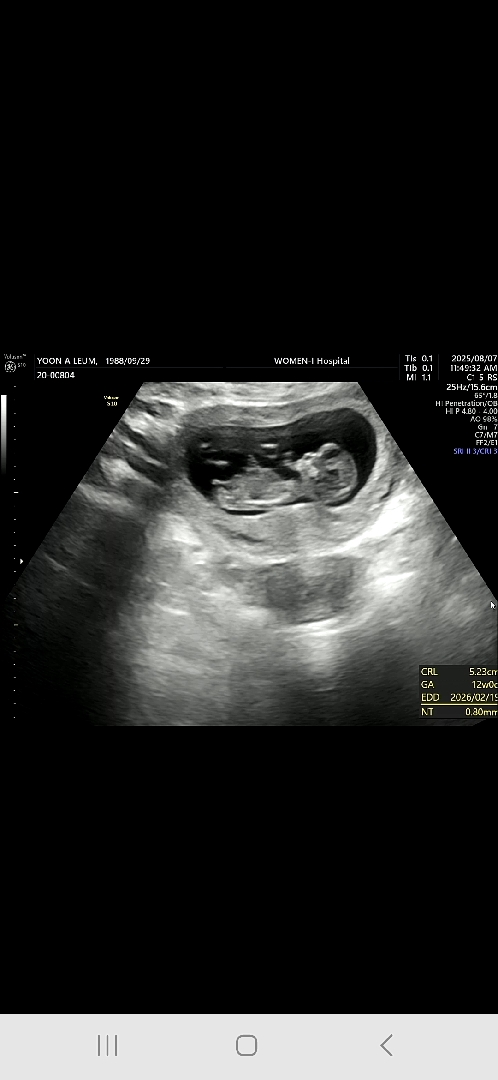

11주5일 성별뭘까요?

성별너무 궁금해요ㅠㅠ

영상에 다리사이 나오길래 캡처 했어요